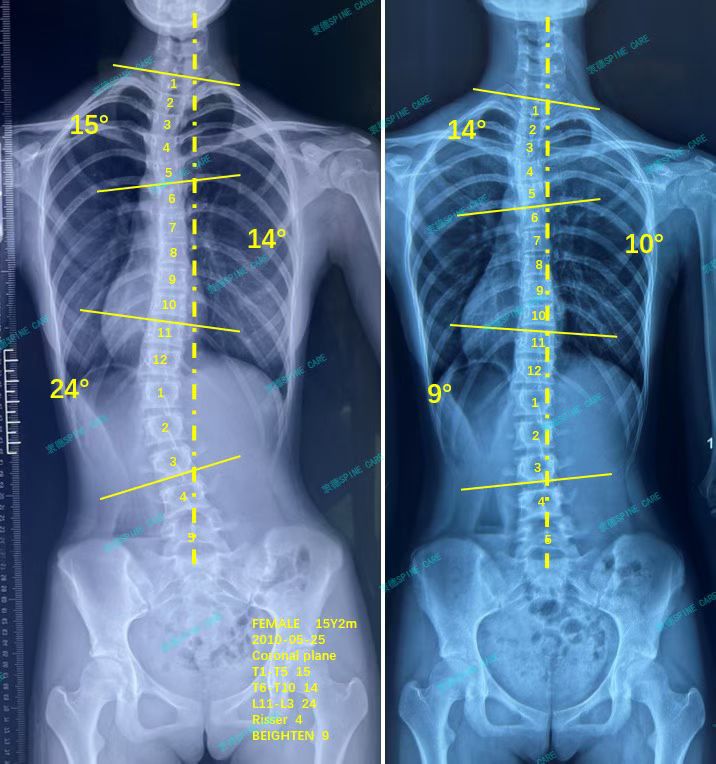

衷德脊柱,我们只关注侧弯保守治疗~

Zhongde Spine, bending no breaking ~